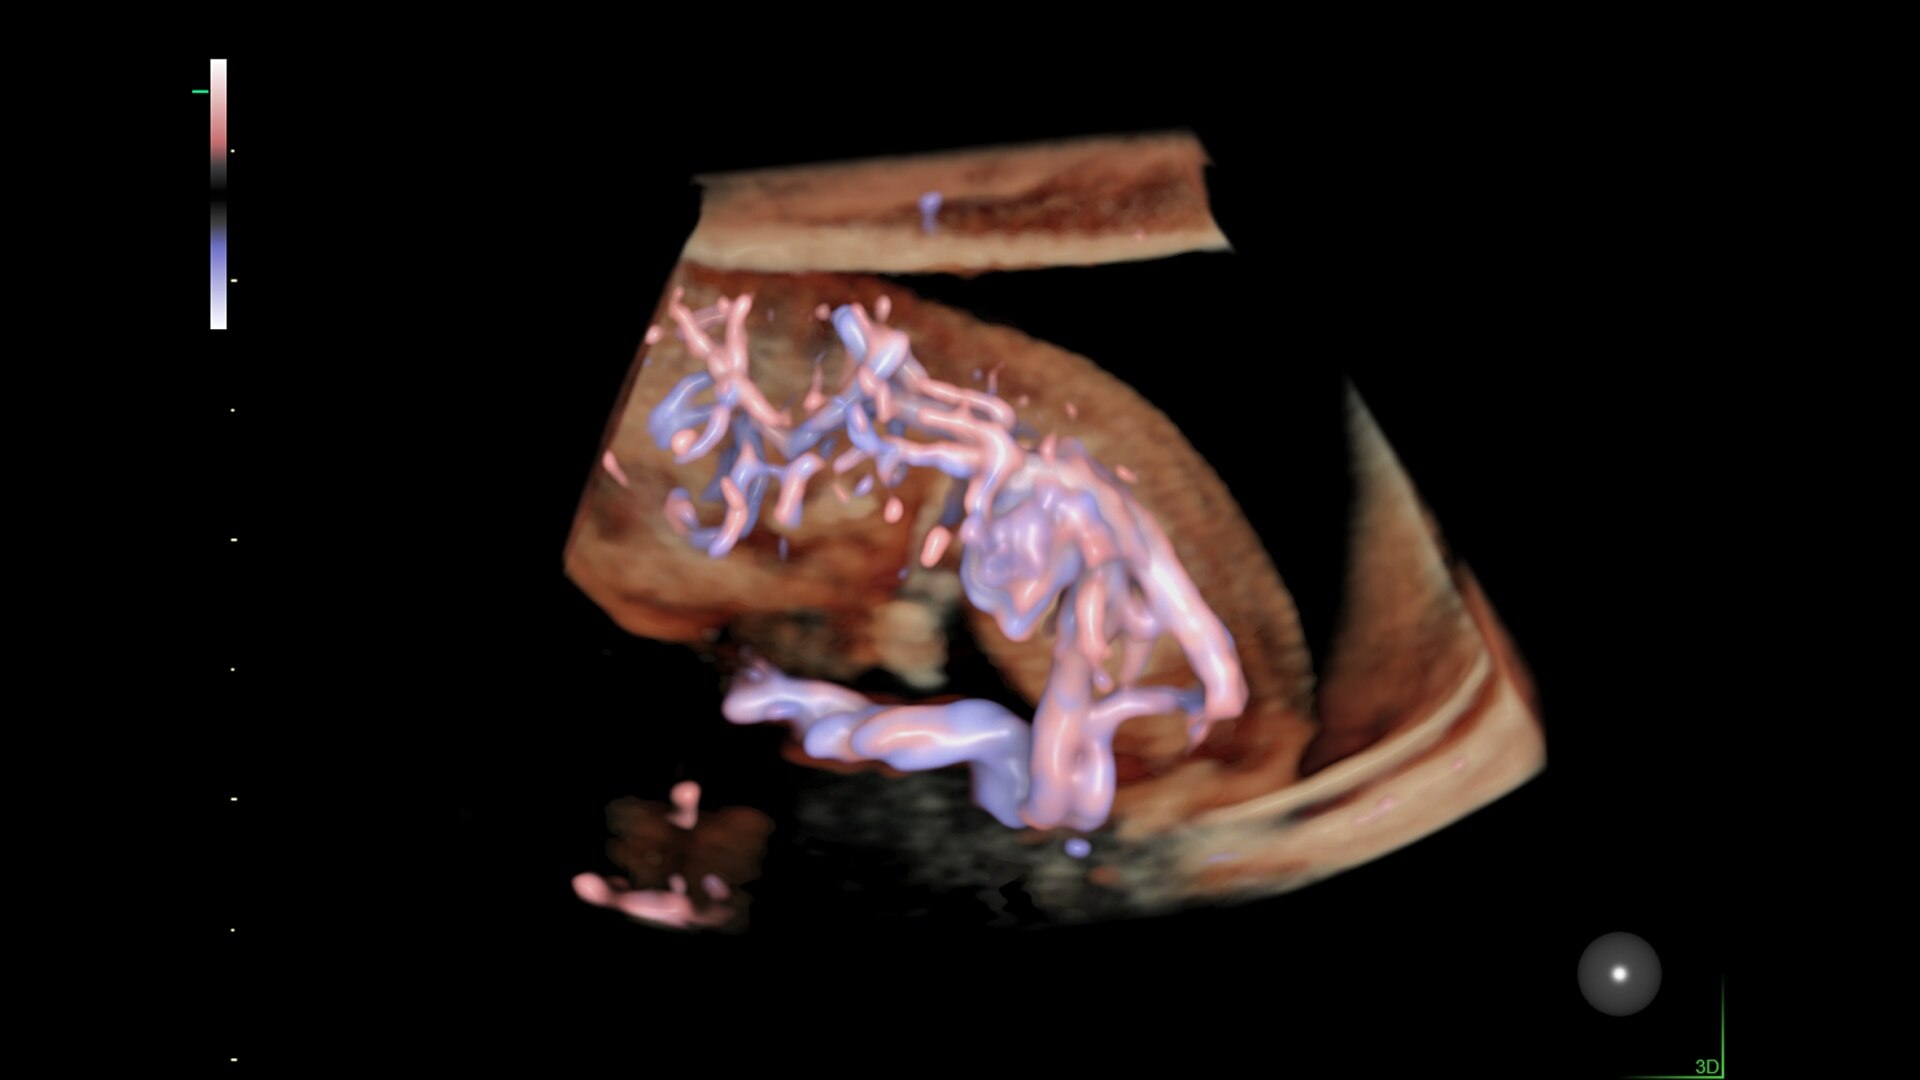

Graphicflow

Hemodynamic Visualization

Provides a graphical representation of the trajectories of the blood cells in real-time to visualize complex blood flow quickly and clearly, helping you to differentiate normal from abnormal hemodynamics